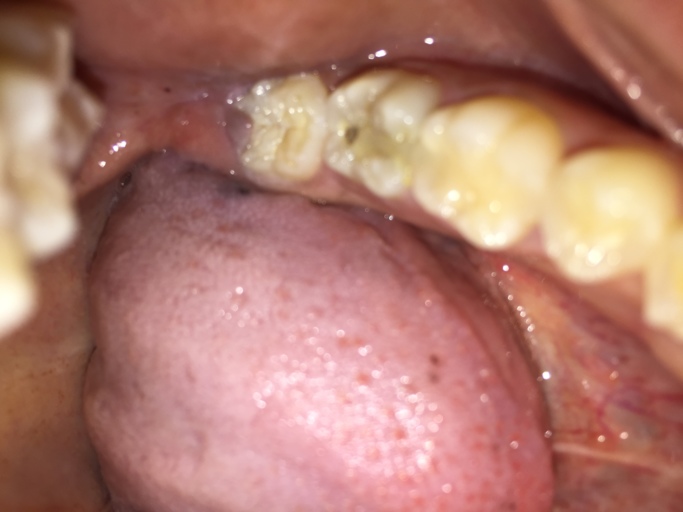

Small Cavity in the Lower Right Molar

Hi there, I am Zaldi and a student at Boise State University, I have a small cavity on the lower right molar tooth, - I want to know how much a filling or cavity treatment is for this case, and - I want to ask if there is any schedule that I can fit into this month so I can set up an appointment with you guys if that is possible. Best, Zaldi